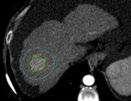

Therefore, having preoperative knowledge of the likelihood of recurrence would assist in selecting the most suitable liver transplant recipients, potentially avoiding unnecessary surgeries, and improving patient prognosis and organ allocation. In this context, radiomics, which involves high-throughput data extraction from medical images, holds great promise.3 However, there is ongoing debate regarding the optimal data selection strategy, as factors such as the choice of contrast phase and volume of interest (VOI) can significantly impact radiomic analysis results.4-6 Therefore, the authors’ study aimed to investigate how these factors influence radiomic features (RF), to identify the optimal combination for predicting HCC recurrence in liver transplant candidates.

Liver transplant candidates from 2010–2019, with waitlist placement CT scans showing nodules suspicious for HCC, according to the Liver Reporting and Data System (LI-RADS) criteria7 (LR-4/-5), and histologically confirmed after the transplant, were retrospectively included. Patients who had previously undergone locoregional procedures, exhibited tumour in vein, or had poor image quality were excluded from the analysis. HCC nodules were contoured

Segmentation Feature Selection Modelling Arterial phase Portal venous phase Delayed phase = Nodule = +5 mm (PT_5) = +10 mm (PT_10) = +15 mm (PT_15) = Background Nodule AP-PVP PVP-DP AP-DP 0% 0% 20% 20% 40% 40% 60% 60% 80% 80% 100% InterVOI MRC >10% Interphase MRC >10% 100% PT_5 PT_10 PT_15 AUC (CI: 95%) P value Pseudo-R2 No. of RFs AP_Nodule 0.77 (0.65–0.90) 0.020 0.23–0.32 8 AP_PT_5 0.90 (0.83–0.97) <0.001 0.33–0.44 8 AP_PT_15 0.88 (0.76–1.00) <0.001 0.36–0.46 12 AP_Nodule_Norm 0.87 (0.75–0.98) <0.001 0.34–0.44 9 DP_Nodule_Norm 0.86 (0.77–0.95) <0.001 0.24–0.35 11 AP_PT_5_Norm 0.88 (0.80–0.97) <0.001 0.31–0.44 8 PVP_PT_10_Norm 0.88 (0.77–0.99) <0.001 0.35–0.45 8 PVP_PT_15_Norm 0.77 (0.65–0.89) 0.002 0.13–0.24 5

Figure 1: Workflow and results from the radiomic analysis of hepatocellular carcinoma nodules and peritumoural regions extracted from the waitlist placement CT scans of liver transplant candidates to predict disease recurrence.

■ = Arterial ■ = Delayed ■ = Portal

■ = Nodule ■ = PT_10 ■ = PT_15 ■ = PT_5

across arterial, venous, and delayed phases, with or without peritumoral region of 5, 10, and 15 mm. An area of ‘background’ liver parenchyma, distant from the lesions, was also segmented in each phase.

A total of 107 RFs, both directly extracted from segmentations, and normalised for the ‘background’ parenchyma, were obtained using PyRadiomics (Python Software Foundation, Beaverton, Oregon, USA). The normalisation was conducted by calculating the ratio between the RFs extracted from the VOI, and those extracted from the background segmentation. These features were then compared with each other for inter-VOIs and inter-phase relative change, while autocorrelation was assessed using Spearman’s rank correlation coefficient. RFs with relative change <10% and rank correlation coefficient >0.90 were considered non-informative. Informative RFs with different distribution in patients with and without posttransplant recurrence were selected to build multiple logistic regression models. Prediction of post-transplant recurrence was assessed by comparing the areas under the curve from receiver operating characteristic analysis and goodness-of-fit, expressed as the value range of Tjur’s, McFadden’s, and Nagelkerke’s R2 .

each comprising 5–12 RFs, with an area under the curve of 0.77–0.90 (p<0.02) and pseudo-R2 values of 0.13–0.46. A predominance of models derived from the arterial phase was observed, utilising the nodule with or without a 5 mm peritumoral region as the VOI, followed by the venous phase, including a 10–15 mm margin after normalisation (Figure 1).

CONCLUSION

Selection of optimal VOI and contrast phase combination is critical to maximise post-liver transplant HCC recurrence prediction using quantitative CT imaging. Specifically, segmenting the nodule, eventually including a 5 mm peritumoral region, during the arterial phase, or the nodule with a 10-15 mm margin during the venous phase after normalisation against the liver background, appeared to be the most promising strategy.●